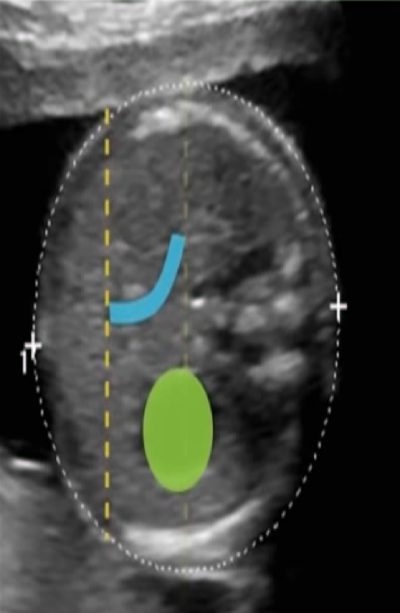

产科超声介绍

2021-12-20

10